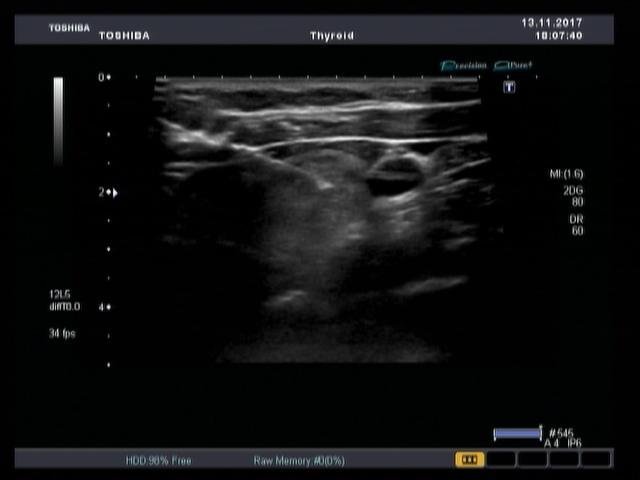

– линейным (для поверхностных органов),

Превосходное качество визуализации — одна из основных причин, благодаря которым системы Aplio стали сегодня одними из самых популярных в мире диагностических ультразвуковых систем премиум класса. Комплексный пакет клинических приложений обеспечивает непревзойденное качество изображений. Полный спектр методов визуализации и количественного анализа позволяют получать данные высокой точности, что способствует принятию обоснованного решения о выборе стратегии лечения заболевания.

Precision Imaging (Прецизионная визуализация) ультразвуковой системы Aplio позволяют получать более реалистичные изображения и обеспечивает высокую степень послойной дифференцировки тканевых структур и анатомическую точность в визуализации деталей.